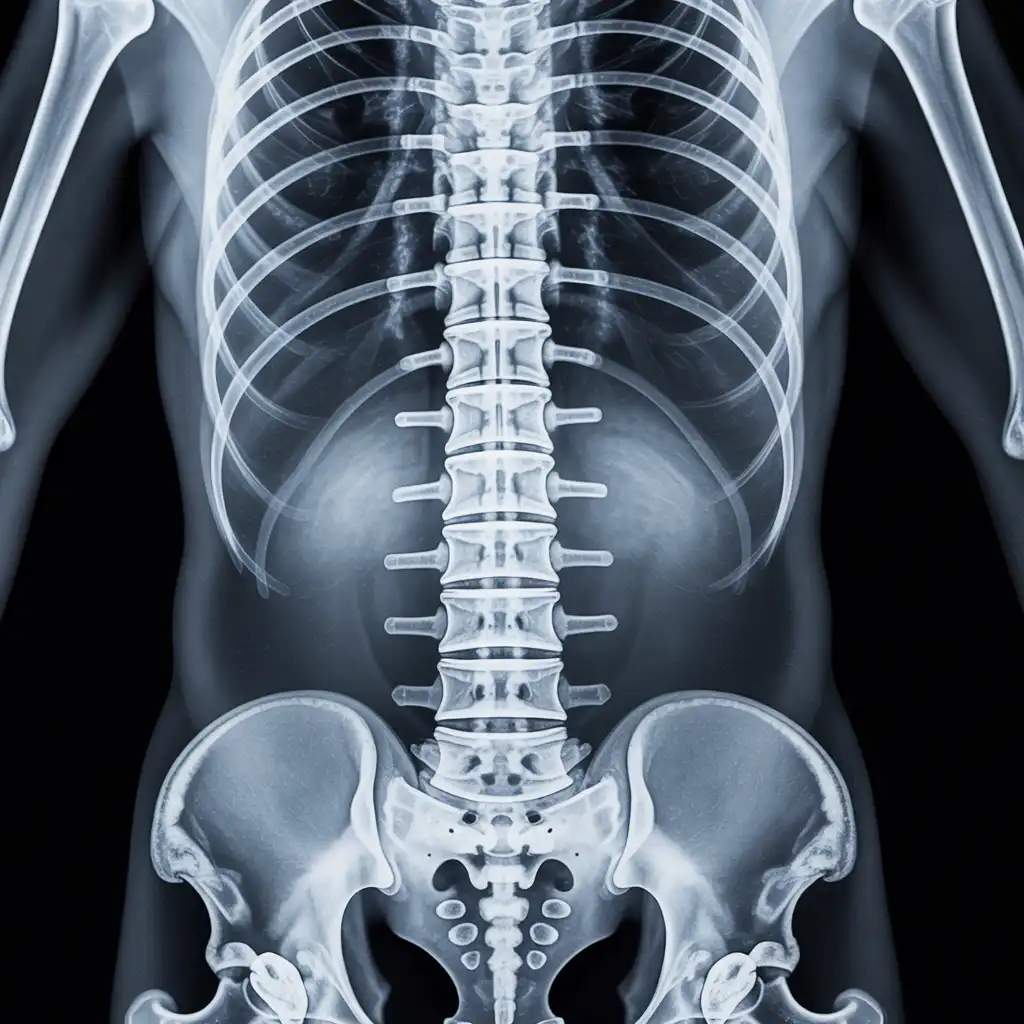

Il professionista entra con apparecchiature a basso dosaggio e schermi protettivi: bastano 2 × 2 m di spazio vicino al letto o alla poltrona. In pochi minuti acquisisce immagini HD, proprio come in un reparto ospedaliero.

Le immagini (formato DICOM) vengono caricate su un server crittografato e inviate immediatamente al radiologo. Se servono scatti aggiuntivi, il tecnico resta in collegamento video per eseguirli al volo.

Il medico radiologo analizza le immagini e firma il referto digitale all’istante. Ricevi il referto cartaceo e le immagini su chiavetta USB consegnati direttamente a casa tua subito dopo l'esame.

Usiamo le stesse apparecchiature certificate CE dei reparti ospedalieri, calibrate regolarmente. I referti sono validi per visite specialistiche, pronto soccorso e pratiche assicurative, e restano archiviati per 10 anni per ogni esigenza futura.